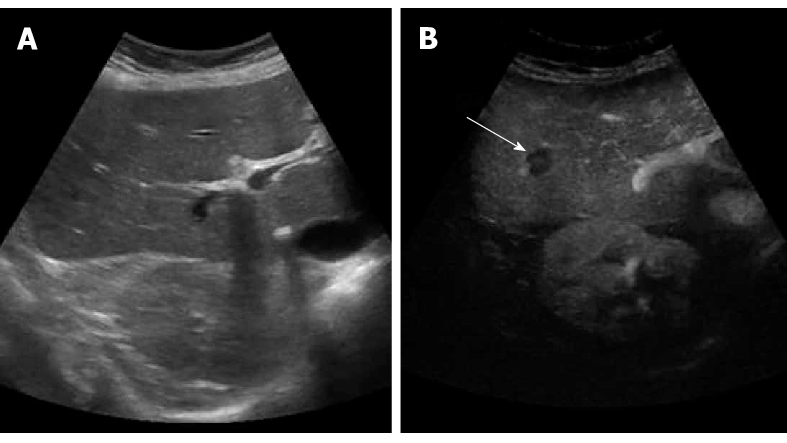

There are two phases to a baseline ultrasound: an abdominal ultrasound and a vaginal ultrasound. To start, we will apply a gel to the patient’s abdomen and run a probe along their midsection. Although the bladder does not need to be full to perform this portion of the ultrasound, it also should not be empty.

After this portion of the ultrasound is complete, the patient is asked to use the restroom. Once the bladder is empty, we will perform the second part of the ultrasound, which involves a vaginal probe. A small vaginal transducer will be placed in the vagina to provide us with a view of the uterus and ovaries.